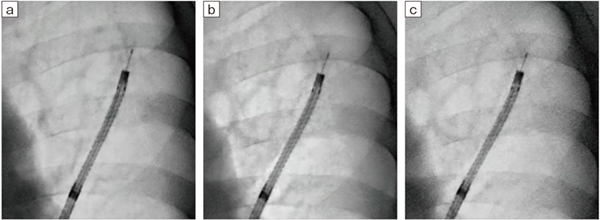

図12 Accent適用症例画像2:各透視線量モードにおける病変とデバイスの視認性の向上

a:Normalモード(3.4mGy/min) b:Midモード(2.1mGy/min) c:Lowモード(1.2mGy/min)

より低線量の透視線量モード(Lowモード)でも視認性が向上しており、病変の位置確認をしながらブラシを視認できる。